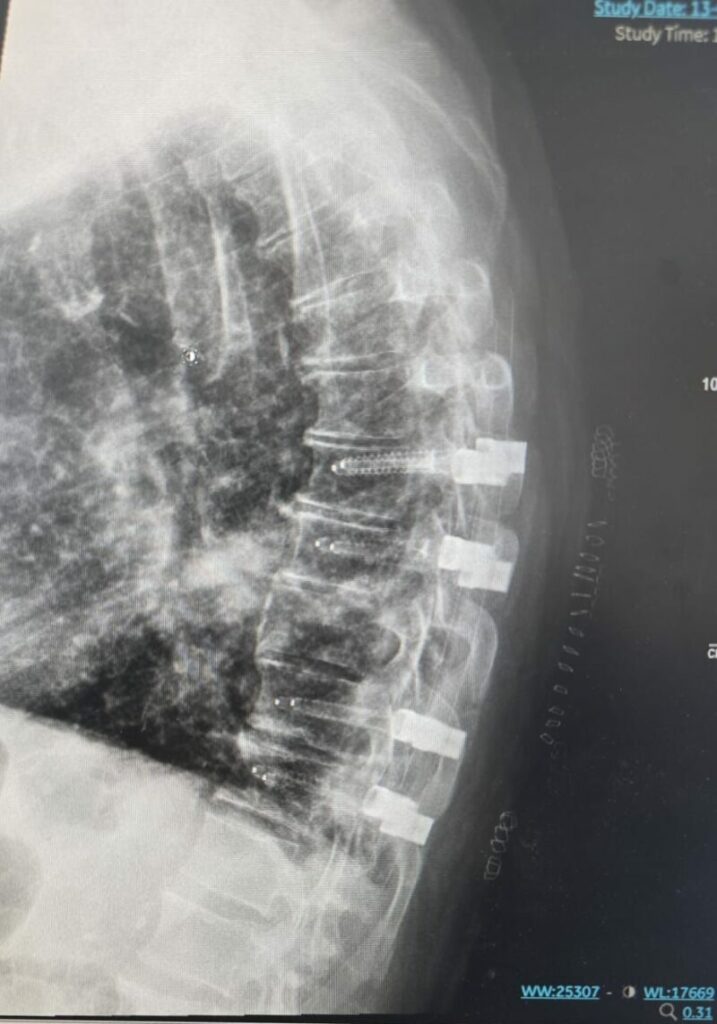

Au cours de l’intervention, les chirurgiens ont implanté huit vis et des tiges en carbone — un matériau jamais utilisé auparavant dans ce type d’opération — par de minuscules incisions d’un centimètre seulement. Parallèlement, ils ont retiré la tumeur comprimant la moelle épinière.

La technologie est issue de la société israélienne CarboFix.

La technique mini-invasive d’insertion de vis rachidiennes par de petites incisions existe depuis près de 30 ans. Elle consiste à introduire une aiguille sous contrôle radiologique, à y placer un fil-guide métallique, puis à insérer la vis et la tige à travers le même passage.

Mais jusqu’à aujourd’hui, personne n’avait réussi à remplacer le métal par des implants en carbone dans ce type d’intervention. Les propriétés physiques complexes du carbone ne permettaient pas son utilisation pour la stabilisation rachidienne par voie mini-invasive.

CarboFix a réussi à relever ce défi. Grâce à ce développement, il devient possible de combiner :

✔ une chirurgie mini-invasive

✔ avec des implants en carbone

— ouvrant une nouvelle ère thérapeutique pour les patients atteints de métastases vertébrales.